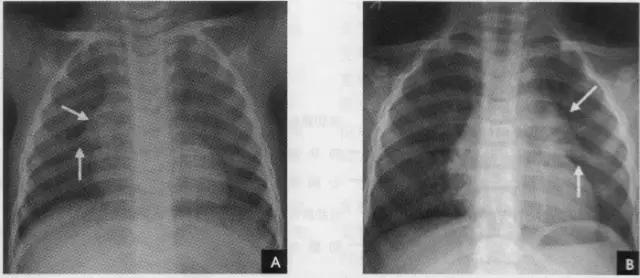

2、横裂又称水平裂,约70%的人正、撼位胸片均可显影。在正位片上表现为右中肺野横行细线状阴影,从第6肋腋部水平自外向内延伸.并止于肺门外lcm处。可向上或向下倾斜10:左右或略成曲线;在侧位片上,横裂起白斜裂中部,向前呈水平方向走行达前胸壁。其位置的改变可作为判断肺体积变化的标志(如上图)。 某些正常人可发生叶间裂不分、分裂不全或出现多余叶间裂等变异情况,因而叶间胸膜也发生相应的变化(参阅肺副叶)。